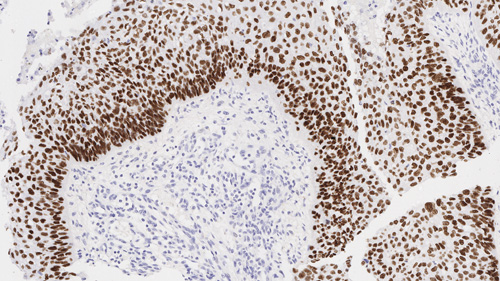

Squamous cell carcinoma of lung: Immunohistochemistry staining of p40. p40: clone BC28

Hintergründe des Antigens

p40 (Delta Np63) ist ein gekürztes Produkt von p63. Es wird für gewöhnlich in der Basal- oder Vorläuferzellschicht von mehrschichtigen Epithelien, in den Basalzellen der Prostata sowie in den Myoepithelzellen der Brust und der Speicheldrüsen, und Zytotrophoblasten in der Plazenta exprimiert und zeigt mit IHC ein nukleares Färbemuster. Unter den zahlreichen Neoplasmen mit positiven p40-Markern können Plattenzellkarzinome mit pulmonalem und nicht-pulmonalem Ursprung von anderen Malignitäten unterschieden werden.

p40 wird für den Nachweis bestimmter Antigene in normalem und neoplastischem Gewebe als zusätzliches Hilfsmittel zur herkömmlichen Histopathologie unter Verwendung nicht-immunologischer histochemischer Färbemittel empfohlen.